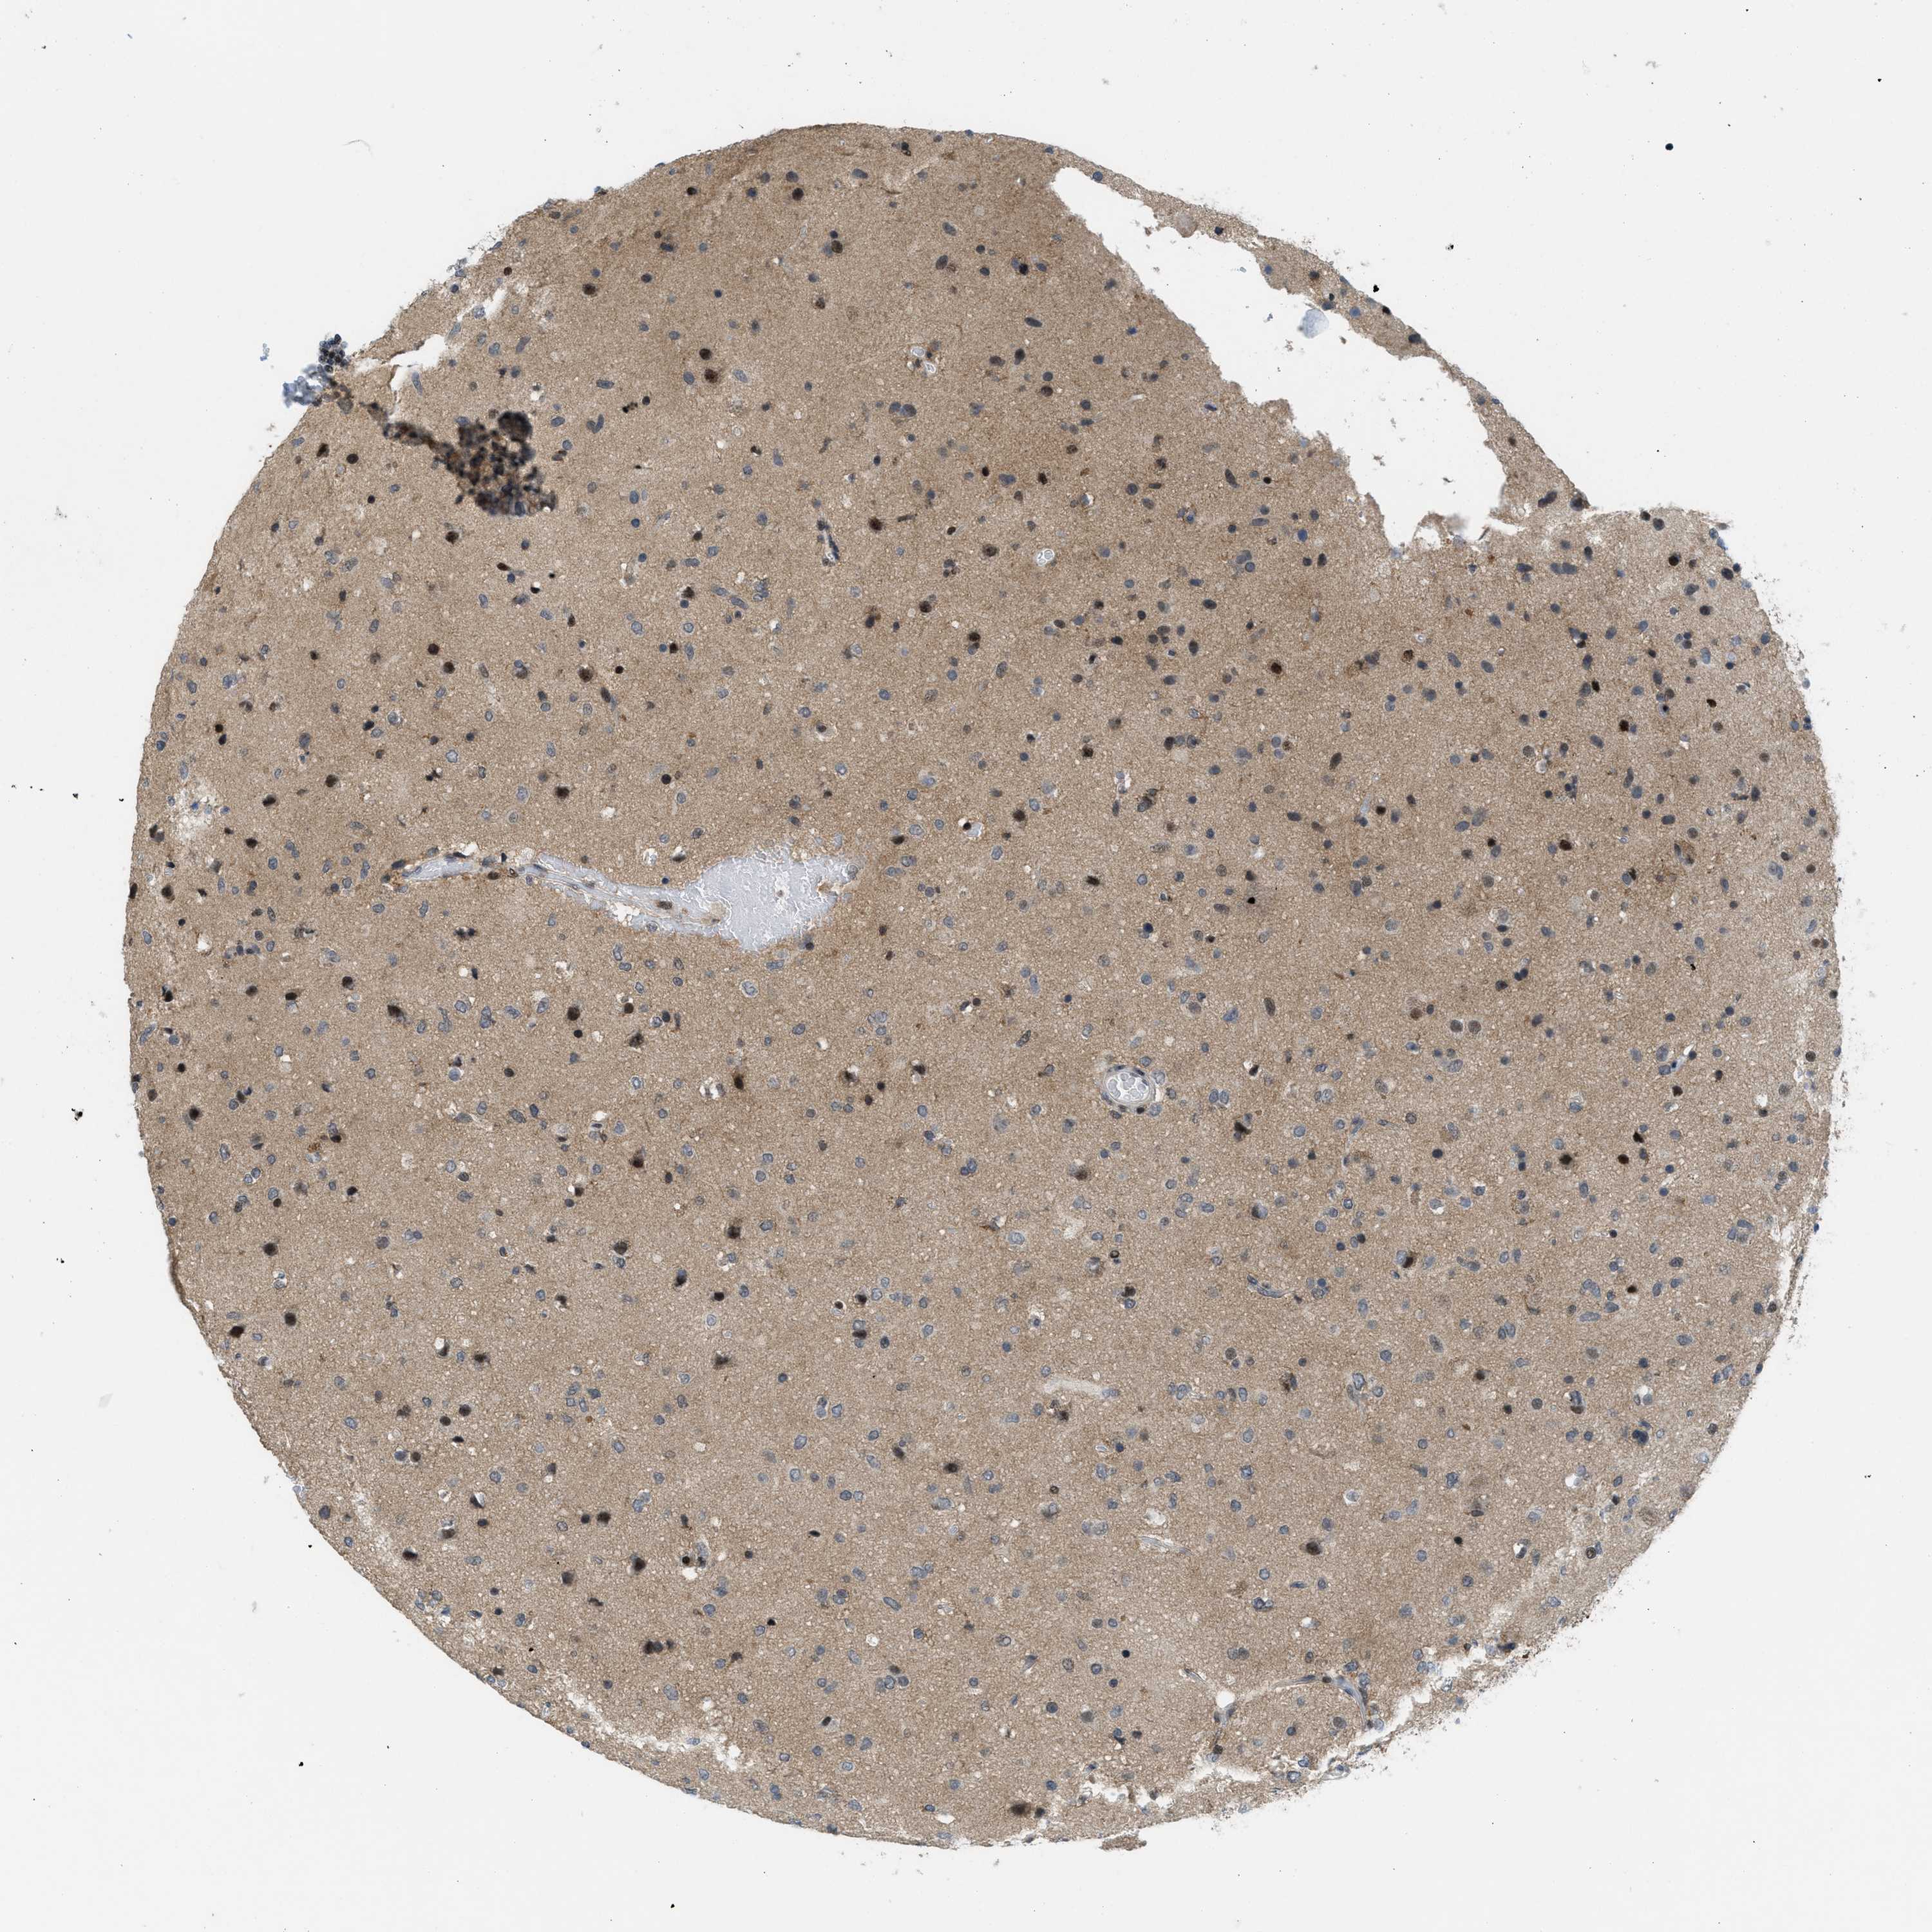

GLIOMA - Protein expressioni

A mouse-over function shows sample information and annotation data. Click on an image to view it in a full screen mode. Samples can be filtered based on level of antibody staining by selecting one or several of the following categories: high, medium, low and not detected. The assay and annotation is described here.

Note that samples used for immunohistochemistry by the Human Protein Atlas do not correspond to samples in the TCGA dataset.

Antibody stainingi

Antibody staining in the annotated cell types in the current human tissue is reported as not detected, low, medium, or high, based on conventional immunohistochemistry profiling in selected tissues. This score is based on the combination of the staining intensity and fraction of stained cells.

Each image is clickable and will lead to virtual microscopy that enables deeper exploration of all samples and also displays staining intensity scores, fraction scores and subcellular localization as well as patient and tissue information for each sample.

Antibody CAB016136

Antibody CAB017773

Staining

High

Medium

Low

Not detected

Intensity

Strong

Moderate

Weak

Negative

Quantity

>75%

75%-25%

<25%

None

Location

Nuclear

Cytoplasmic/membranous

Cytoplasmic/membranous,nuclear

Glioma, malignant, High grade

Glioma, malignant, Low grade